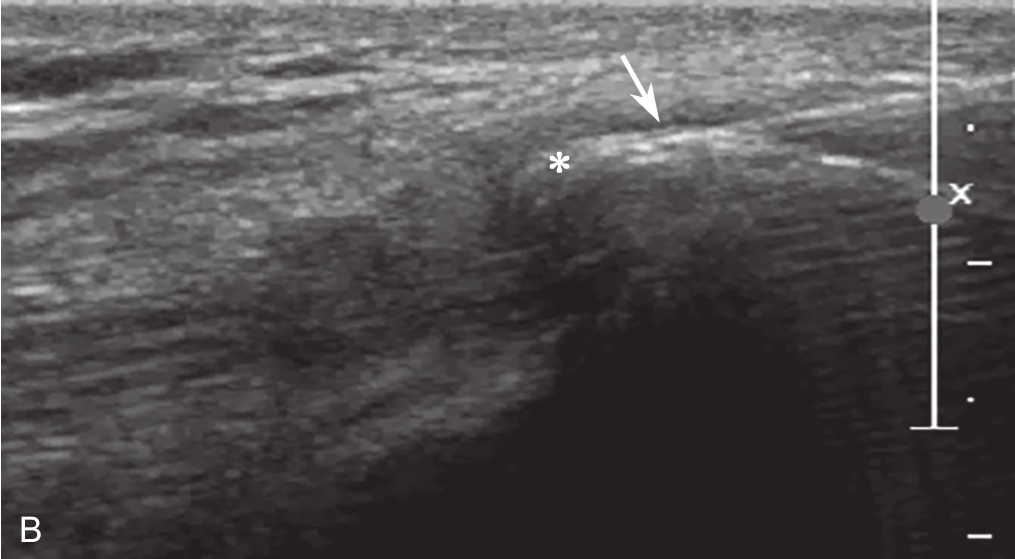

▲ 图2-2-7 超声引导下股四头肌钙化性肌腱炎介入治疗

A.操作图;B.超声图;星号:钙化灶;箭头:穿刺针

▲ 图2-2-8 超声引导下髂肌钙化性肌腱炎介入治疗

A.操作图;B、C.超声图;星号:钙化灶;箭头:穿刺针;D.穿刺出的乳白色黏稠钙化物质